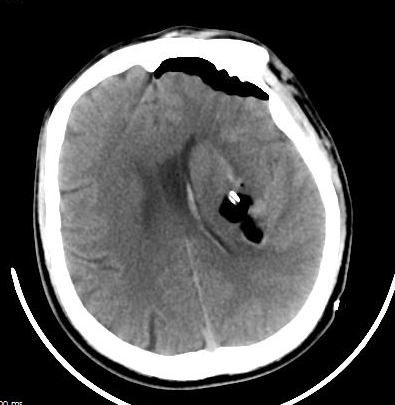

該名46歲男性患者,因“突發(fā)意識(shí)障礙伴惡心、嘔吐3小時(shí)”來(lái)醫(yī)院急診科就診,急診頭顱CT顯示“左側(cè)基底節(jié)區(qū)腦出血(出血量約43ml)”。急診完善頭頸部CTA排除腦血管畸形、動(dòng)脈瘤后,緊急收入神經(jīng)外科并即刻實(shí)施“神經(jīng)內(nèi)鏡下腦內(nèi)血腫清除術(shù)”,手術(shù)順利。術(shù)后患者神志清楚,頭部手術(shù)切口僅5cm左右。復(fù)查頭顱CT提示顱內(nèi)血腫大部分清除,經(jīng)術(shù)后積極對(duì)癥治療后痊愈出院。

圖2:術(shù)后CT提示顱內(nèi)血腫大部分清除。